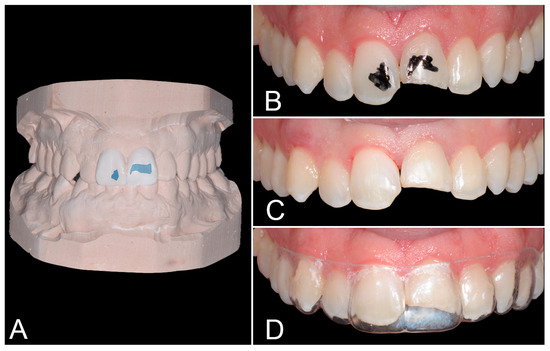

2. Case Report